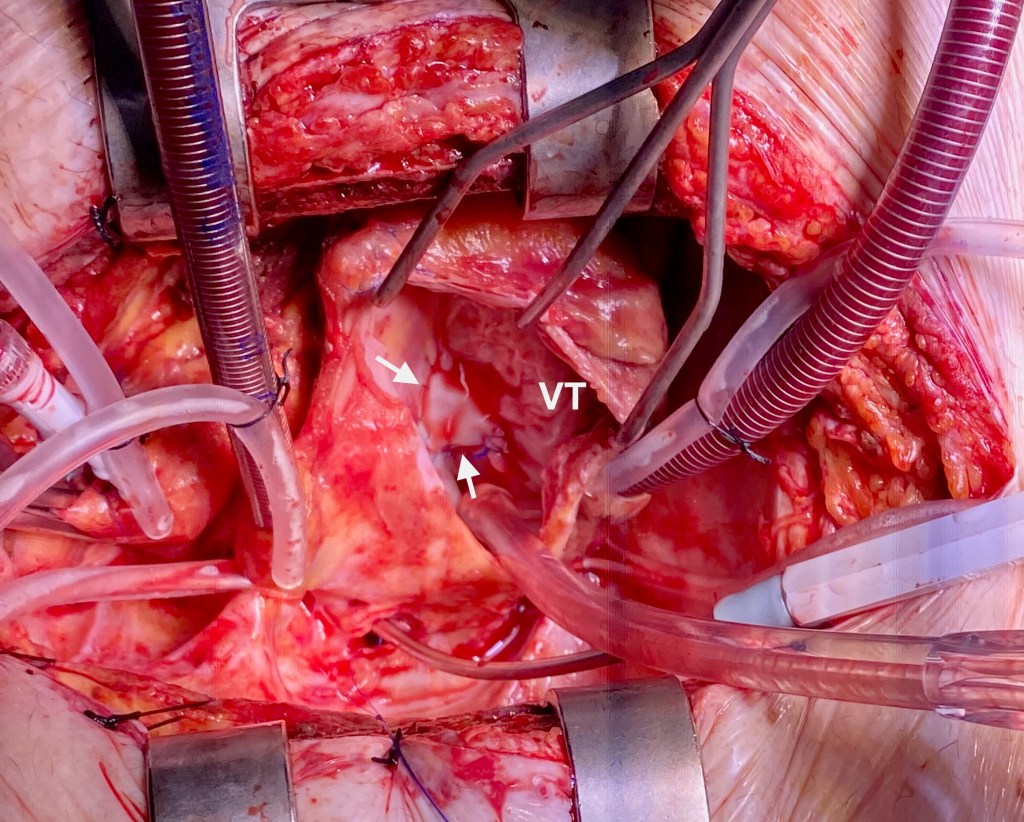

El caso publicado hace referencia a un varón de 68 años, portador de una valvulopatía aórtica moderada en seguimiento y antecedentes de una neurocirugía reciente para resección de una malformación arteriovenosa cerebral, que ingresó en la UCI de nuestro hospital con el diagnóstico de endocarditis infecciosa de la válvula aórtica por Staphilococcus aureus meticilin-resistente. El paciente estaba en situación de parada cardiorespiratoria en el contexto de un bloqueo aurículo-ventricular completo, lo que obligó a la implantación de un marcapasos transitorio. Posteriormente sufrió una crisis tónico-clónica, que obligó a su intubación oro-traqueal. El ecocardiograma demostró la existencia de una insuficiencia aórtica masiva, por lo que se sometió a un reemplazo valvular aórtico emergente. La evolución postoperatoria fue buena, pero una semana después, en un eco de control, se detectó una masa en la aurícula derecha asociada a una comunicación tipo Gerbode directo o supravalvular. Inicialmente se decidió manejo conservador, pero a los 15 días del diagnóstico, coincidiendo con un claro empeoramiento clínico, se objetivó importante aumento del cortocircuito intracardiaco, por lo que el paciente se sometió a una nueva cirugía para corrección quirúrgica del defecto mediante cierre del orificio de salida en la aurícula derecha. El eco de control post-cirugía mostró una prótesis aórtica normofuncionante, ausencia de shunt residual y una válvula tricúspide competente. La evolución posterior discurrió sin incidencias y el paciente fue dado de alta al finalizar el tratamiento antibiótico.